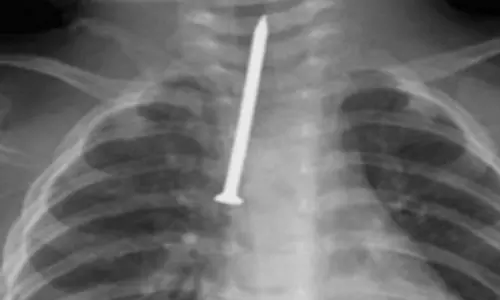

റിയാദ്: ശ്വാസനാളത്തിൽ ആണി കുടുങ്ങി അതീവ ഗുരുതരാവസ്ഥയിലായ എട്ടുമാസം പ്രായമുള്ള കുഞ്ഞിനെ സങ്കീർണമായ ശസ്ത്രക്രിയയിലൂടെ...